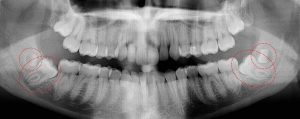

This 21 year old patient has all four 3rd molars present (circled). The roots are approximately 2/3rds formed. The lower right 3rd molar cannot erupt any further; it is distally tipped into the ramus of the mandible. The lower left 3rd molar likely will not erupt any further; it is pushing into the undercut of the distal of the 2nd molar.